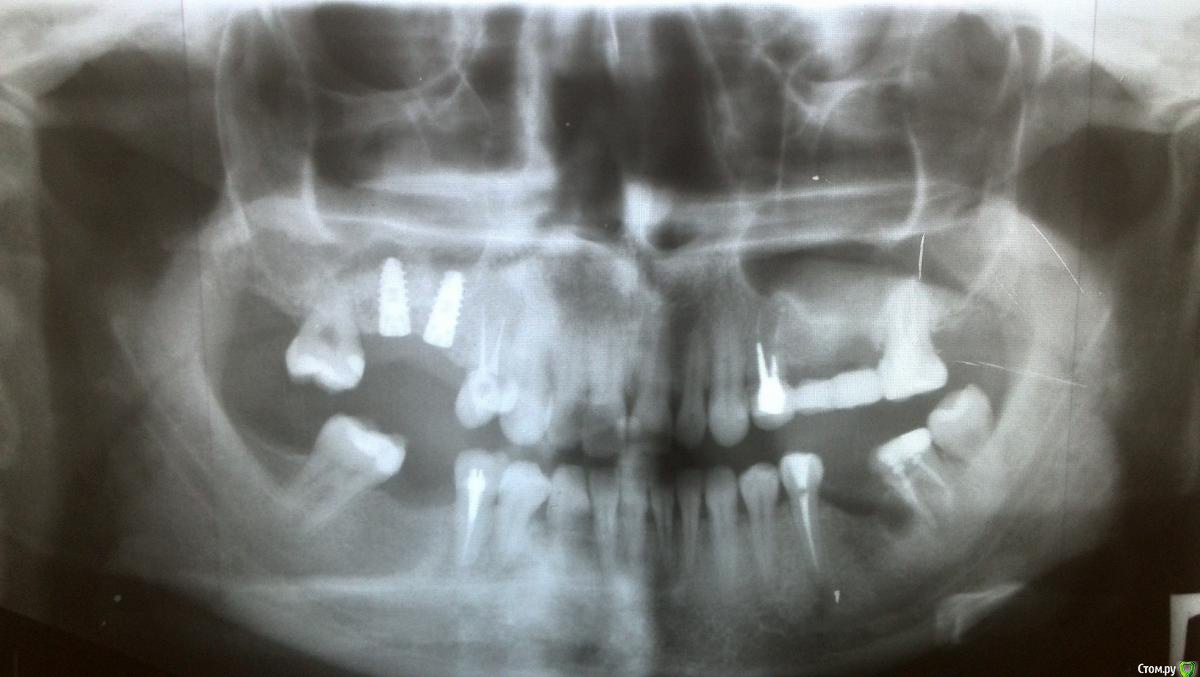

Анчетка Опубликовано 17 марта, 2015 Поделиться Опубликовано 17 марта, 2015 Добрый день, пожалуйста ответьте на вопрос ,были ли такие ситуации в практике ,что после синус лифтинга костная крошка выходила из носа ,но в дальнейшем не было осложнений ,все нормально заросло-прижилось. Сегодня четвертый день после синус лифтинга и одновременной установки двух имплантов , на третий день и сегодня со сгустками крови из носа выходит костная крошка , других осложнений нет ,температура в норме, синяка и припухлости не было , сделали панораму -врач сказал продолжать пить антибиотики .Заранее благодарю за уделенное время. Ссылка на комментарий